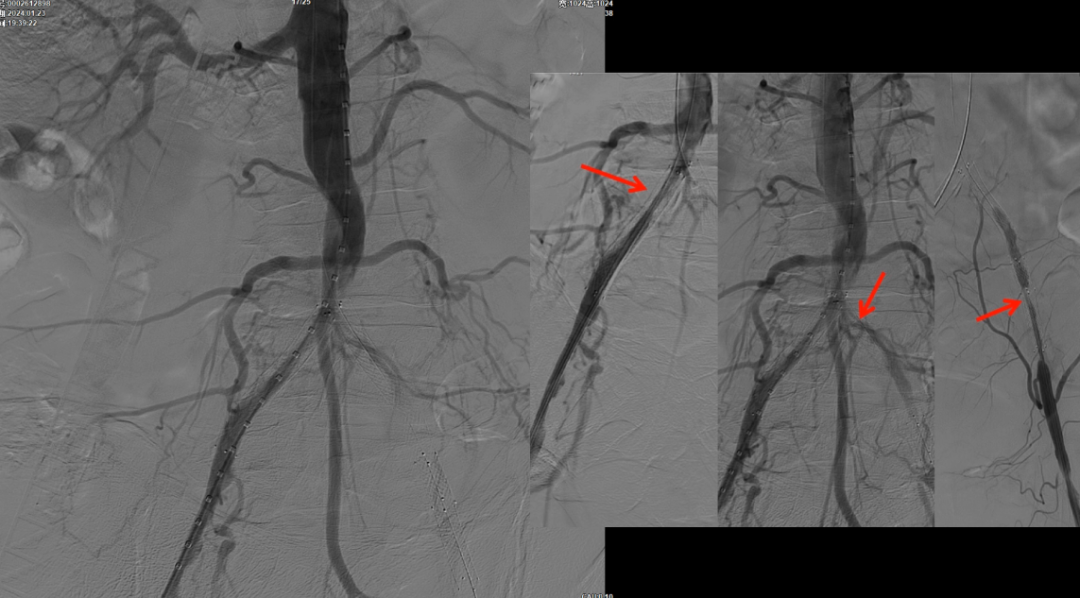

减容后造影显示仍存在重度残存狭窄,遂沿右侧股动脉置入VBX支架(直径11mm,长度59mm)。支架定位需满足近端完全覆盖腹主动脉病变段,远端距离双侧髂总动脉分叉至少1.5cm,以避免后扩张时大球囊对髂动脉造成损伤。

该图解释为何远端距离双侧髂总动脉分叉至少1.5cm,以避免后扩张时大球囊对髂动脉造成损伤。

CERAB技术的关键点一:经双侧股总动脉植入2枚VBX球囊扩张式覆膜支架(8L×79mm),与腹主动脉覆膜支架腔内平行放置,且两枚支架端平齐对接。

CERAB技术关键点二:先用14mm×40mm球囊分别扩张双侧髂肢的腹主动脉段。

再用8mm球囊对双侧髂支腹主动脉段行对吻扩张,以确保双侧髂支与腹主动脉覆膜支架腔内获得良好的贴壁形态,最大程度减少空腔,降低远期再狭窄发生率。

右侧髂外动脉存在残存狭窄,因该部位无原有裸支架覆盖,为节省治疗费用,选择植入1枚直径8mm的裸支架,并采用8mm球囊进行后扩张。

即时效果:造影显示腹主动脉、双侧髂总/髂外动脉及股动脉通畅。